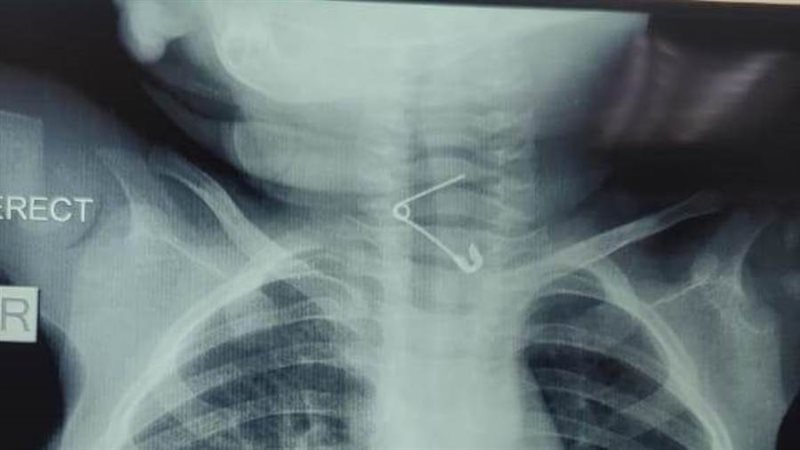

عمره عام.. إنقاذ حياة رضيع ابتلع "دبوس" بمستشفى الأطفال التخصصي ببنها

نجح فريق طبي بقسم جراحة الأطفال بمستشفى الأطفال التخصصى ببنها في محافظة القليوبية، في إنقاذ حياة طفل بلغ من العمر عامًا، ابتلع دبوسًا معدنيًا استقر في الحلق، مهددًا مسار التنفس ومسببًا خطورة بالغة على حياته.

ضم الفريق الطبي قيادة الدكتور محمد متولي، رئيس قسم جراحة الأطفال ونائب مدير المستشفى، وبإشراف الدكتور محمود البرنس، مدير المستشفى، حيث تجهّز الفريق الجراحي خلال دقائق معدودة لخوض هذا التحدي الدقيق، إذ تولّى الجراحة كل من الدكتور وليد محمد والدكتور محمد أيمن.